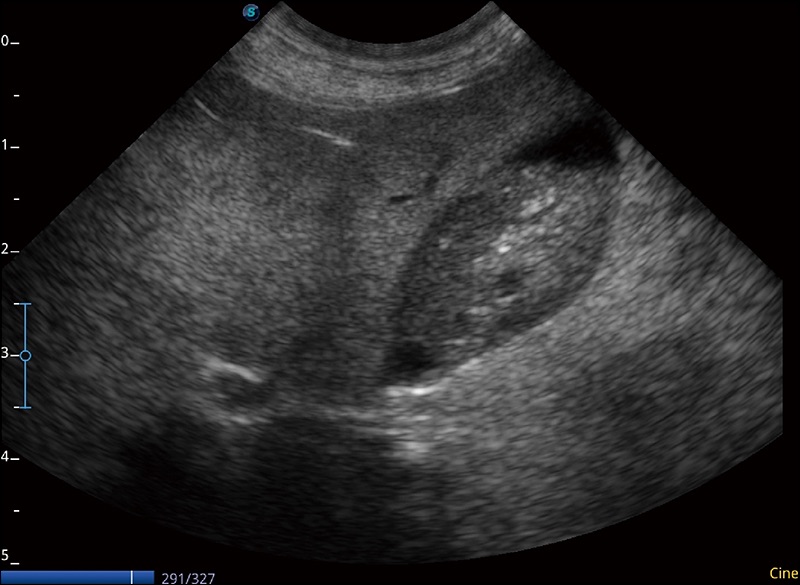

α1卓越的图像质量和便捷的工作流程,使每位宠物医生都能轻松扫查。其全面的兽用应用功能和紧凑型的结构设计,可以满足动物检查的多种需要。专业的预设检查模式和多领域测量软件包有助于为不同类型的动物提供检查, 让宠物医生能够出色的完成工作。

可实时观察感兴趣区域和病变位置